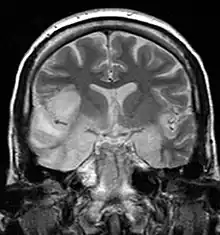

| MRI scan image shows high signal in the temporal lobes and right inferior frontal gyrus in someone with herpes simplex encephalitis. | |

Limbic encephalitis refers to inflammatory disease confined to the limbic system of the brain. The clinical presentation often includes disorientation, disinhibition, memory loss, seizures, and behavioral anomalies. MRI imaging reveals T2 hyperintensity in the structures of the medial temporal lobes, and in some cases, other limbic structures. Some cases of limbic encephalitis are of autoimmune origin.[18]

- Brain scan, done by MRI, can determine inflammation and differentiate from other possible causes.